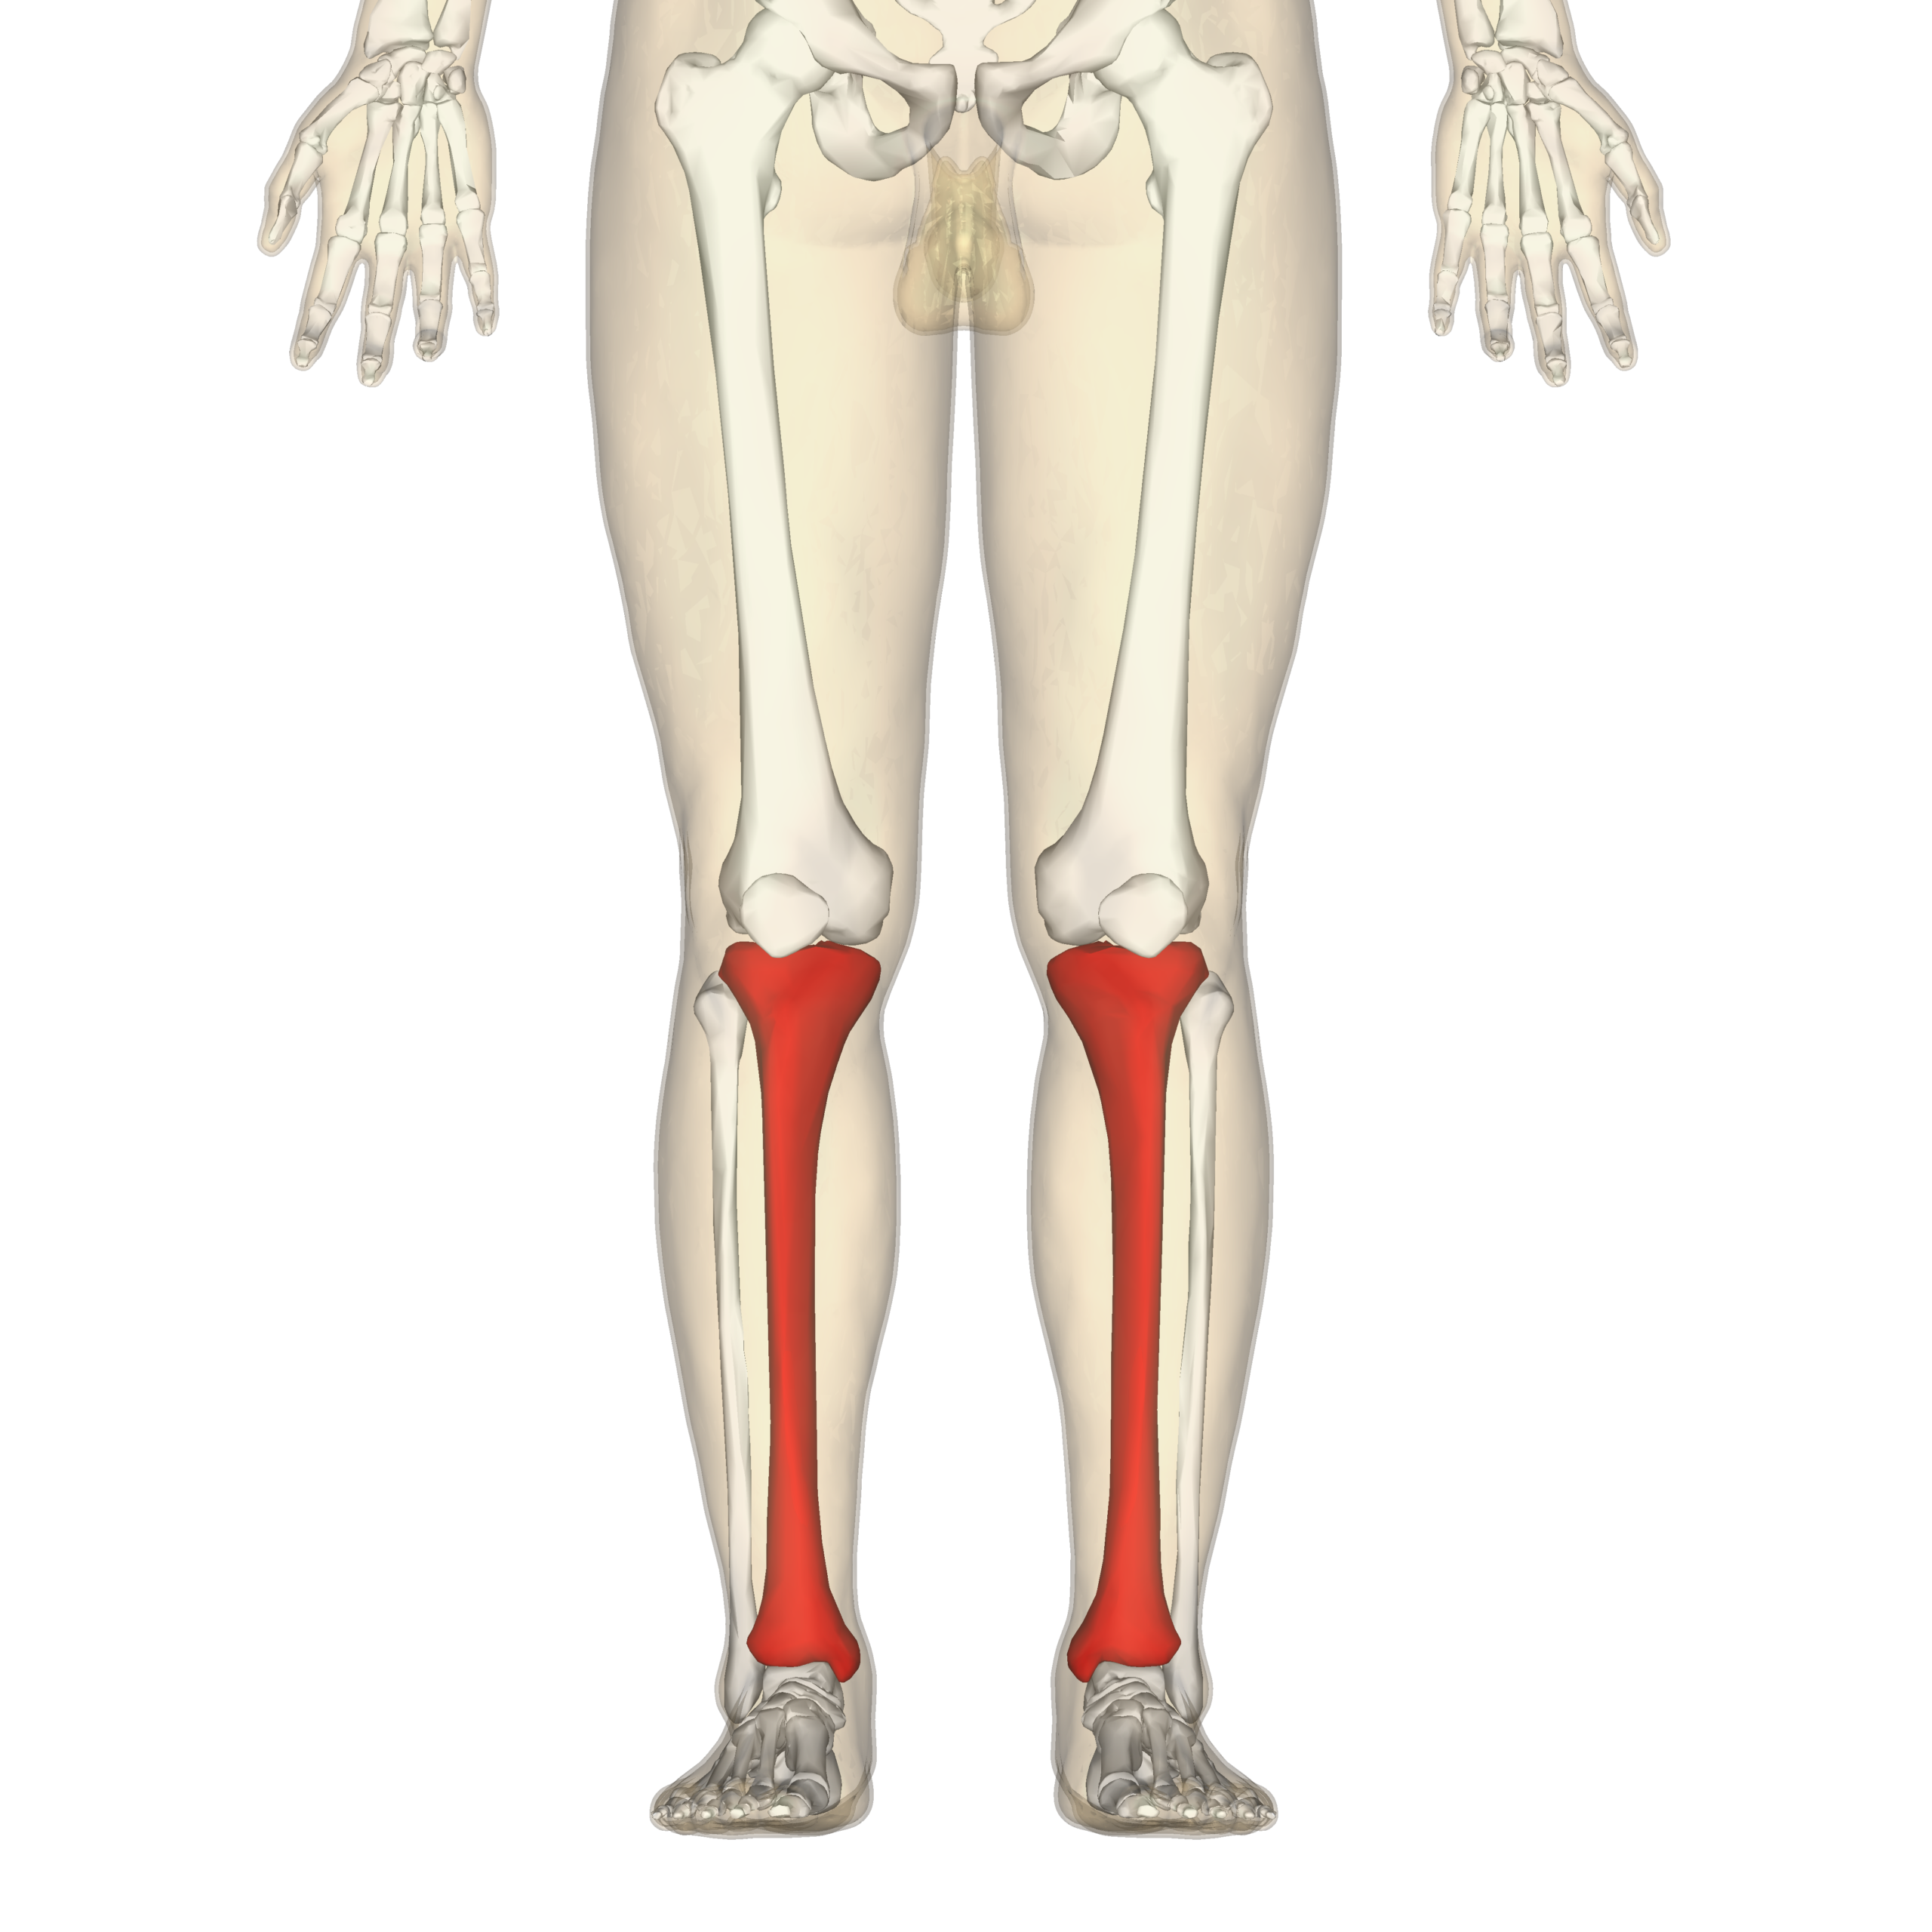

When faced with a clue like “shinbone crossword clue,” it’s essential to think outside the box and consider all possible meanings. The shinbone, also known as the tibia, is a vital part of the human body located in the lower leg.

One strategy to solve this clue is to look for synonyms or related terms that could point you in the right direction. Words like “leg bone” or “lower limb bone” might just lead you to the correct answer.

Tibia Wikipedia